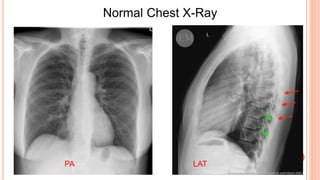

Normal Chest X-Ray

PA LAT

3)Position: PA, AP, or lateral

view? The standard chest X-Rays

consists of a PA and lateral chest X-

Ray.

The normal lateral chest x-ray view is

obtained with the left chest against

the cassette. If the x-ray is a true

lateral, the right ribs are larger due to

magnification and usually projected

posteriorly to the left ribs (Figure-3).

• #23 The right ribs (red arrows) and left ribs (green arrows) on the lateral chest X-Ray.